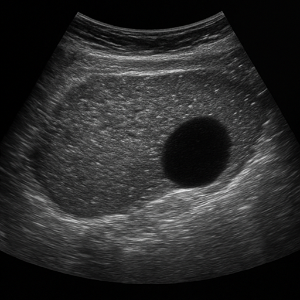

간은 복부초음파에서 가장 먼저 살펴보는 장기예요. 초음파로 지방간, 간경변, 결절, 낭종, 혈관종, 간암 등 여러 가지 변화를 감지할 수 있고, 간 기능 검사에 이상이 있을 때 특히 중요하게 확인해요.

간에 기름이 쌓이면 초음파에서 밝고 반짝이는 모습으로 보일 수 있어요. 요즘 지방간이 흔한데, 초음파로 쉽게 확인되서 유용합니다. - 간경변

만성 염증으로 간이 딱딱해지고 울퉁불퉁해지는 상태예요. 초음파에서 간 표면이 거칠고 모양이 변형된 모습으로 나타나요. - 간암(간 종양)

덩어리나 혹처럼 생긴 이상이 초음파 화면에 포착될 수 있어요. 양성 종양인지 악성인지 구분하려면 추가 검사가 필요할 때도 있어요.

- 복부 종양(낭종, 종양)

간, 신장, 또는 다른 복부 장기에 생긴 혹들은 초음파에서 덩어리로 보여요. 가끔은 원래 장기가 아닌 곳에 생긴 종양도 보여요. - 복수 (복강 내 물)